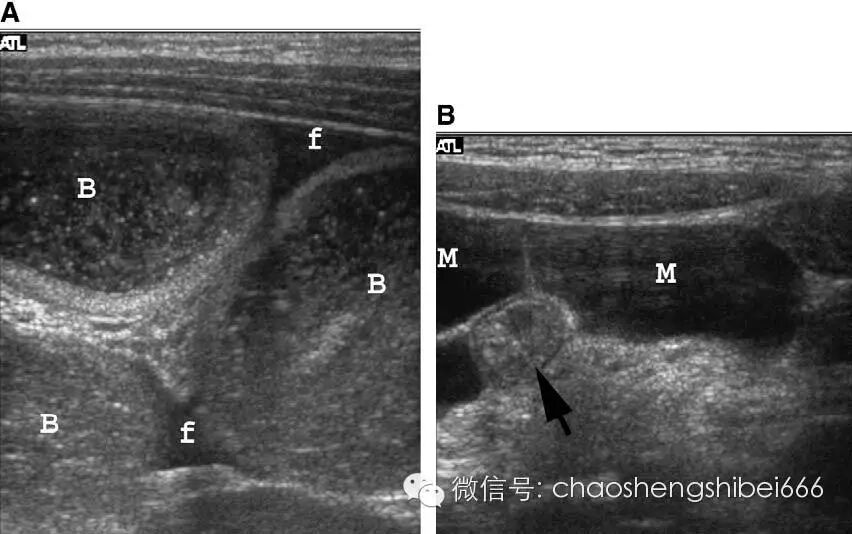

临床评价儿童小肠梗阻多不采用超声检查,因为临床病史和物理检查结果都可使临床大夫考虑梗阻的存在。前面讨论的许多疾病都可以导致肠梗阻。超声声像图上出现充满液体的扩张的肠袢可以提示肠梗阻,特别是发现肠管管径明显变化的部位以及远端的肠袢塌陷。超声检查可以帮助明确肠梗阻的病因(图12)。

12 3岁的小肠梗阻患儿。梗阻继发于肠系膜囊肿引起的局部肠扭转。

A 梗阻导致肠管增宽,内部可见内容物(B),F 液体

B 肠系膜囊肿(M)呈有分隔的液性无回声,部分包绕一段正常肠管(箭头)